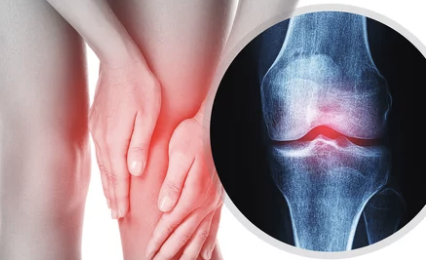

관절염은 크게 퇴행성 관절염과 류마티스 관절염으로 나눌 수 있으며, 각각의 원인과 증상, 치료 방법에 차이가 있습니다.

- 퇴행성 관절염: 관절 연골이 닳아 없어지면서 발생하는 질환으로, 주로 노화나 관절 과사용으로 인해 발생합니다. 통증은 주로 활동 후 심해지고 휴식을 취하면 완화되는 경향이 있습니다. 무릎, 엉덩이, 손, 척추 등 체중 부하가 많이 가해지는 관절에 흔하게 발생합니다.

- 류마티스 관절염: 면역 체계 이상으로 관절에 염증이 발생하는 자가면역 질환입니다. 통증은 아침에 심하고 활동하면서 완화되는 경향이 있으며, 여러 관절에 동시에 발생하고 전신 피로감, 발열 등을 동반할 수 있습니다. 손목, 손가락, 발목, 발가락 등 작은 관절에 흔하게 발생합니다.